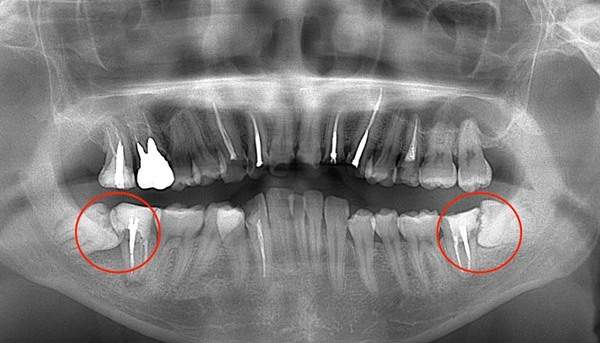

下顎の親知らずが斜めにはえてしまっている症例です。前の歯との間が過去に虫歯になってしまい、神経をすでに取っている状態です。親知らずを残したことで再び虫歯になっていました。

また、前の歯の根の先端の方まで骨が溶けてしまっています(智歯周囲炎)。虫歯と歯周病を併発してしまっているのです。このように他の残さないといけない歯に悪影響を与えている親知らずはなるべく早めに抜くのが良いでしょう。

症例

症例01